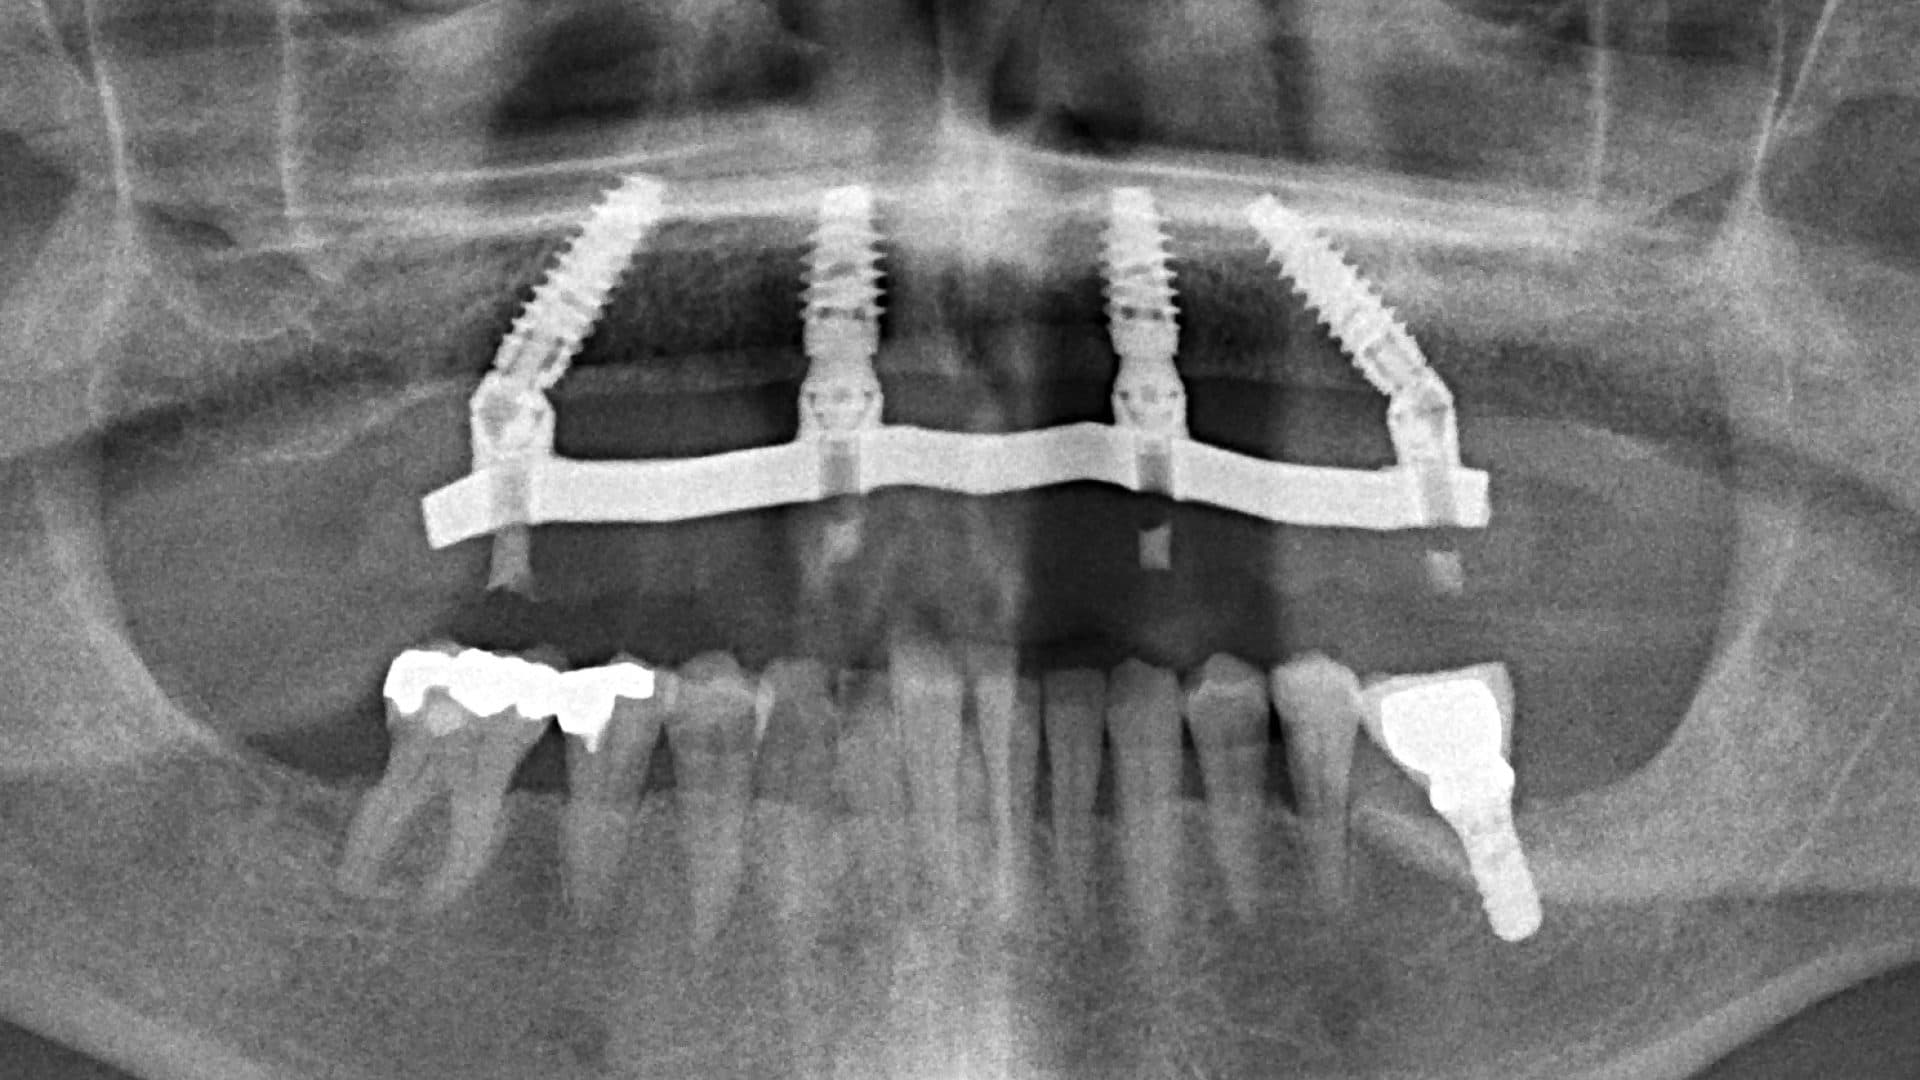

iii. Alignment on x-rays: there should be even spread, rigid connection between the implants, good bone levels, and the height of the prosthesis should be at least as tall as the shortest fixture (See pictures).

Ideal Situation